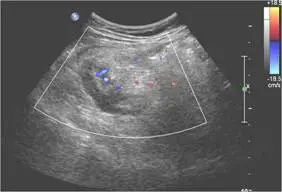

46歲女性病人主訴於月經過後下腹部疼痛,尤其右下腹部疼痛約3天,身體診察右下腹部有壓痛現象,右下腹部超音波檢查如圖,最可能的診斷為何?

- 第三張彩色多普勒影像顯示闌尾壁層明顯血流信號(continuous intramural flow),符合急性闌尾炎高特異性之血管增生表徵(pubmed.ncbi.nlm.nih.gov)。

以上影像符合急性闌尾炎的主要超音波徵象:盲端非蠕動管狀結構、外徑≥7 mm、壁層厚化及周圍炎性回聲增高,並有彩色多普勒顯示之局部高血流。